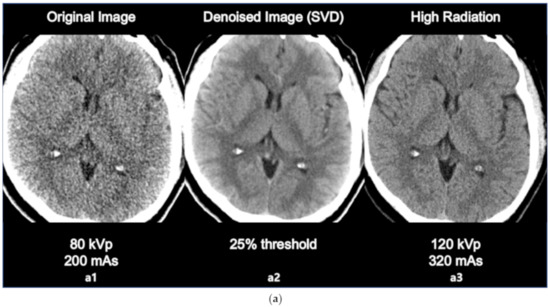

The comparison between original image, denoised image, and high radiation dose image is as in the following Figure 4a,b. The sharpness of ventricle and parenchyma margin, the distinctness of basal ganglia and parenchyma in the denoised image, and the differentiation of gray matter and white matter in the denoised image was clearly described close to original high dose image.

(a) Comparison between the original image (80 kVp, 200 mAs, a1 the denoised image using SVD (25% threshold, a2, and the high dose image (120 kVp, 320 mAs, a3). (b) Comparison between the original image (80 kVp, 200 mAs, b1), the denoised image using SVD (25% threshold, b2), and the high dose image (120 kVp, 320 mAs, b3).

The results of the SNR and CNR estimations are presented in Figure 5a,b. In Figure 5a, the mean SNRs at the basal ganglia level exhibited a significant increasing tendency except for the 15% and 30% threshold values. The largest improvement involving a significant 16% increase (t = 2.908, p < 0.005) was observed at the 40% threshold setting. Similarly, in Figure 5b, the mean CNRs at the basal ganglia level maintained an increasing tendency for every threshold setting. The largest improvement involving a significant 43% increase (t = 6.327, p < 0.001) was also observed at the 40% threshold setting. However, image a6 that is labeled as 25% of the threshold value resulted in the best statistical significance per the results of the paired t test (t = 3.764, p < 0.001), resulting in an adequate 14% increase in the SNR. Considering the example dataset presented in Figure 3a, even though the 40% setting resulted in the highest SNR, the 25% setting appeared to generate more diagnostic information associated with the vessels. The 25% setting also resulted in good CNR estimation results with a statistically significant 37% increase (t = 6.080, p < 0.001). Based on these findings, we considered that the 25% setting could potentially be the optimal setting for 4D axial CTP images at the basal ganglia level in terms of compromising between noise reduction and preserving diagnostic information. In addition, we would like to highlight that we were able to achieve a considerable improvement in quantitative image quality in the denoised images without having to increase the radiation dose. Figure 4a,b shows the comparison of the original image with the lower dose image (80 kVp, 200 mAs, a1), the denoised image (80 kVp, 200 mAs, 25% of threshold, a2), and the higher dose image (120 kVp, 320 mAs, a3). Regarding Figure 4a,b, we would like to believe that we were able to improve the diagnostic value of low dose (Figure 4a,b, a2, b2) image similar to the ones scanned with high dose (Figure 4a,b, a3, b3) by using the proposed SVD-denoising technique. In other words, there is potential to preserve sufficient image quality even in scans involving lower tube currents. Lowering the tube current and tube voltage is the simplest way to reduce the radiation dose involved in a CT scan. Based on the fact that the amount of noise on an image is inversely proportional to the square root of the radiation dose, reducing tube current and tube voltage can inevitably lead to the degradation of image quality, thereby generating a larger amount of noise on the image [30,31]. Considering this, additional studies to investigate the qualitative and quantitative comparison between the denoised lower dose image and higher dose image on CTP may be meaningful. Additionally, further study with artificial biological objects using 3D bioprinting will be required for more accurate evaluation.